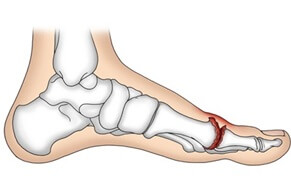

A break in the long bone connecting the midfoot to the toes

Causes: Twisting injuries, landing awkwardly, direct blow to outer foot

Symptoms: difficulty walking, outer foot pain, swelling and bruising

Full Article: Fifth Metatarsal Fractures